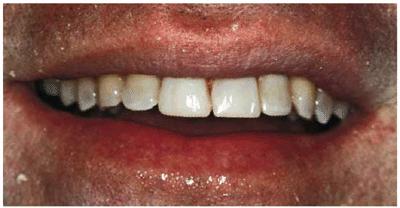

Figur 323s1823d e 18-5A: This 65-year-old man had fractured his right central incisor. Because he desired a younger and brighter looking smile, six porcelain laminates were treatment planned.

Figur 323s1823d e 18-5B: This patient had an end-to-end bite, which required additional incisal edge reinforcement.

Figur 323s1823d e 18-5C: Note the improvement in this man's smile with a lighter shade and teeth that are more proportionate to each other.